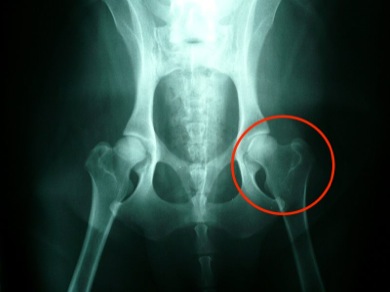

Next, x-rays of the pelvis are taken. Radiography is the only true means of reaching a definitive diagnosis of CHD. On x-ray, a healthy hip joint shows a snug fit of the femur head against the acetabulum, with the acetabulum appearing to cover about three-fourths of the femur head. In dysplastic dogs, the femur head appears to jut away from the acetabulum, and more space is visible between the two bones. Displacement of the head of the femur is considered the hallmark of CHD.

2 Photo Credit: Veterinary Practice News